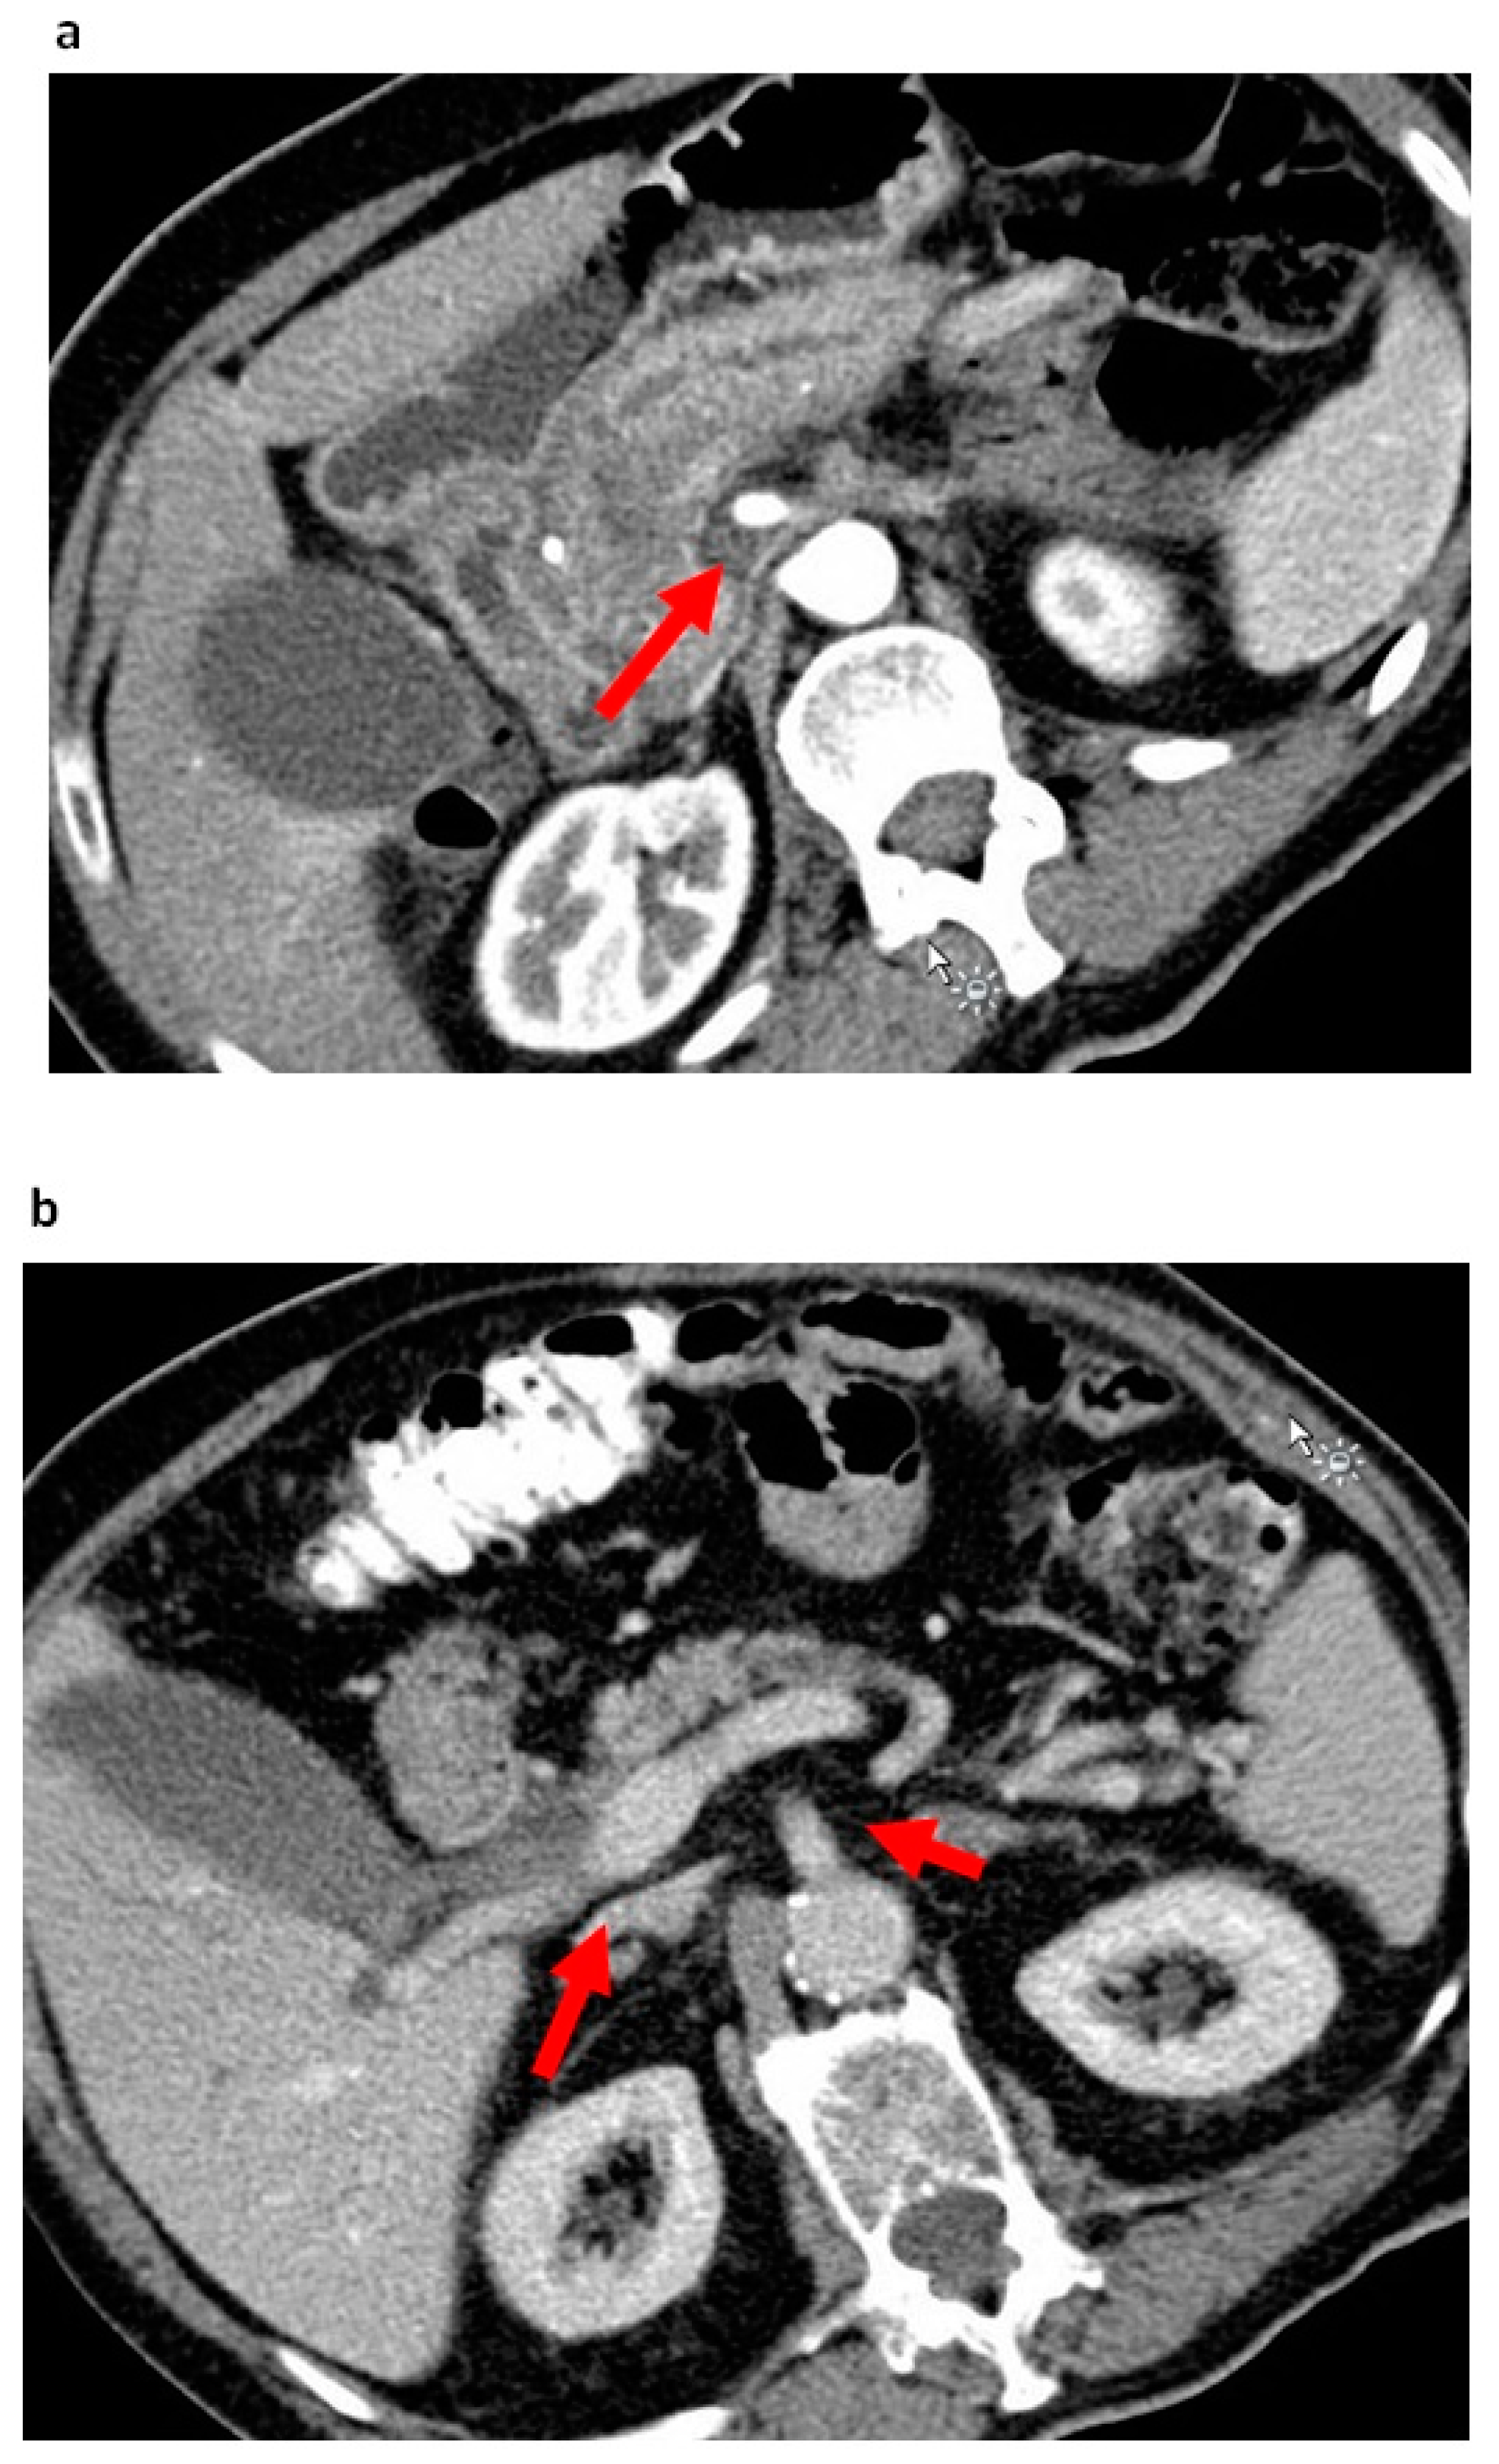

- Kato, T.; Ban, D.; Tateishi, U.; Ogura, T.; Ogawa, K.; Ono, H.; Mitsunori, Y.; Kudo, A.; Tanaka, S.; Tanabe, M. Reticular pattern around superior mesenteric artery in computed tomography imaging predicting poor prognosis of pancreatic head cancer. J. Hepatobiliary Pancreat. Sci. 2020, 27, 114–123. [Google Scholar] [CrossRef]

- Wellner, U.F.; Krauss, T.; Csanadi, A.; Lapshyn, H.; Bolm, L.; Timme, S.; Kulemann, B.; Hoeppner, J.; Kuesters, S.; Seifert, G.; et al. Mesopancreatic stromal clearance defines curative resection of pancreatic head cancer and can be predicted preoperatively by radiologic parameters: A retrospective study. Medicine 2016, 95, e2529. [Google Scholar] [CrossRef]